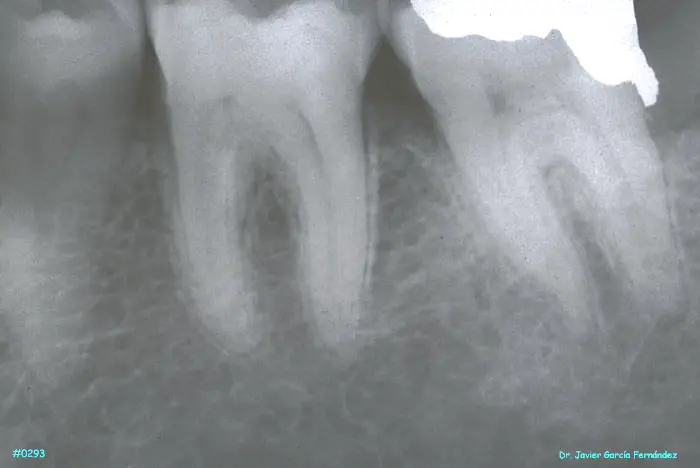

ATLAS DE CIRUGIA PERIODONTAL

image338